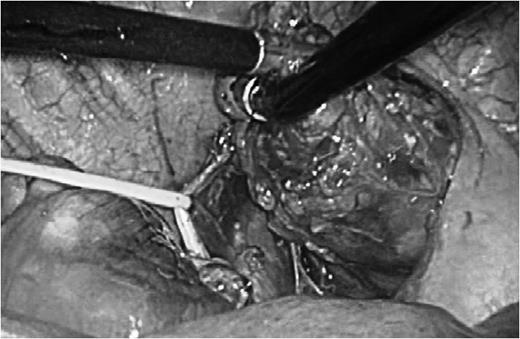

To resect this tumor, we started surgery using the thoracoscopic lateral approach from the right side. There was no intrapleural adhesion or pleural effusion, and the tumor was easily detected in the mediastinum, behind the superior vena cava (SVC) anterior to the trachea. After opening of the superior mediastinal pleura, the azygos vein was dissected using Endo-GIA Tri-Staple camel 45 mm (Covidien, Dublin). Without any significant invasion to the adjacent mediastinal structures, it was possible to dissect the tumor from the trachea, SVC and right brachiocephalic vein (Fig. 2). However, the edge of this tumor was so deep that dissection of this tumor from the brachiocephalic trunk was impossible only with the right thoracoscopic lateral approach. Then, a subsequent median sternotomy was performed to remove this tumor. Intraoperative quick pathological examination diagnosed it as a thymoma. An extended thymectomy was performed additionally.

Intraoperative findings. Dissecting the tumor from surrounding structures. The vagus nerve was taped.